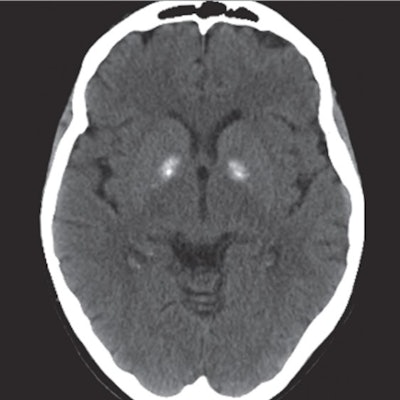

By the time the woman arrived in the U.S. she was stuporous and needed intubation. She was rushed to the hospital, where CT imaging revealed bilateral hyperdensity of the globus pallidi.

Careful evaluation of the clustering of the woman's signs and symptoms helped clinicians uncover pesticides as a likely cause of her illness. One of those signs was the CT scan, which indicated senile calcifications of the globus pallidu. Other signs of acute cholinergic toxicity included depressed mental status, bradycardia, miosis, and twitching.